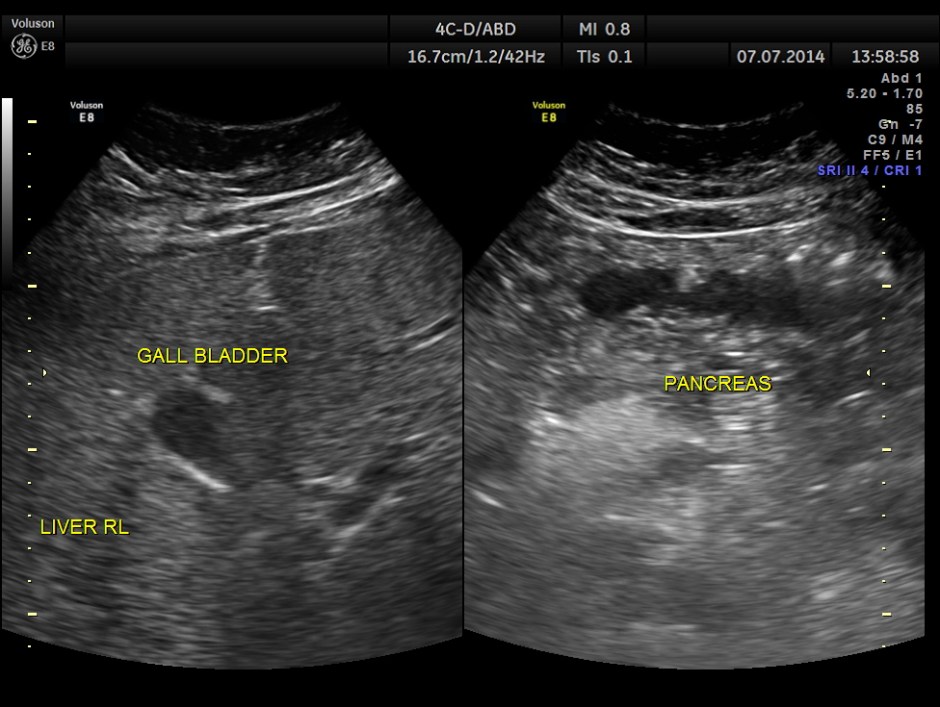

The urinary bladder showed ? mass lesion at first look.

With change of position this ” mass ” was seen to roll within the urinary bladder , suggestive of blood clot.

In this patient the increased vascularity is brought out very well by glass body imaging . Clots of blood seen in the urinary bladder gave the false impression of a mass lesion in the bladder initially.The importance of a dynamic study of turning the patient to the sides should always be remembered.